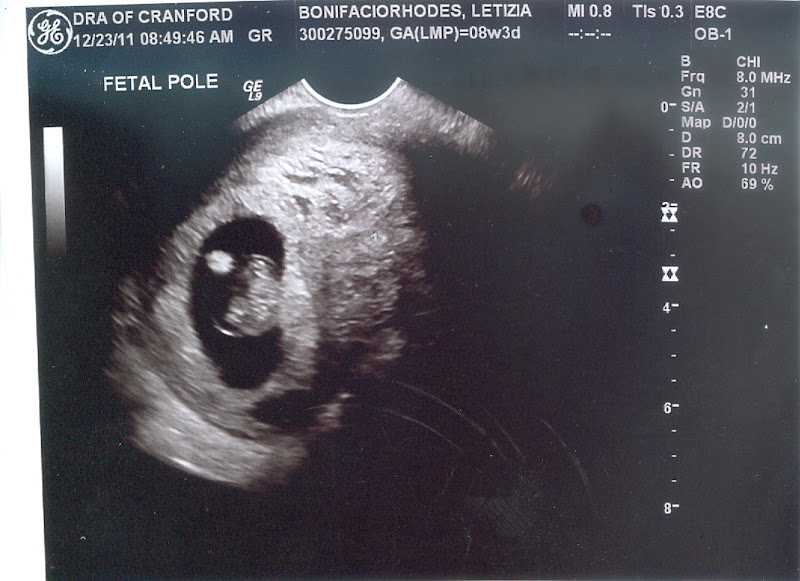

Here is my first look at my baby.

The best part of being pregnant are the ultrasounds!! Hearing the heartbeat still amazes me that women grow a little baby in their belly. I was nervous hoping everything was OK. Having that one miscarriage around the same time is nerve-racking. Everything went well while I was there what a relief.

Since I had all these issues last time my doctor wanted to test me for everything earlier. Londyn was born preterm at 36 1/2 week & low birth weight. So they tested me for some bacteria ureaplasma & I tested positive. I looked it up & it said it's most likely result of low birth weight, miscarriage, preterm labor. They put me on medication to make it go away. Then they mentioned I have low potassium again & a hemorrhage. Thank God the hemorrhage this time around didn't make me bleed, it scared me so much I thought I miscarried last time. So although I seem to already have issues they aren't anything I'm not used to. I'm just nervous if this bacteria doesn't go away will I go earlier then I did with Londyn.